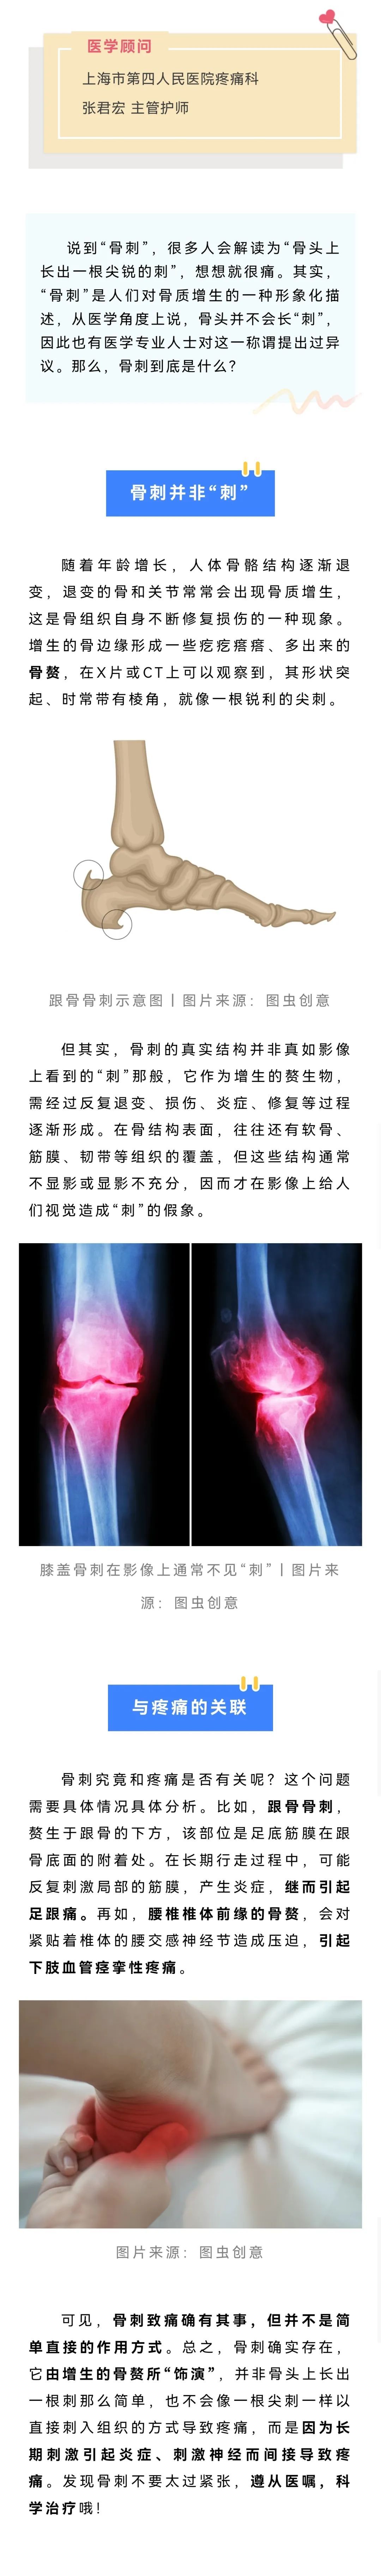

刚才有个病人在那疑惑呢,他说为啥片子拍出来没长刺,但是被诊断有“骨刺”。

骨刺并非“骨头长刺”的意思,看来很多人对骨刺有误解,我们请专家来说说~